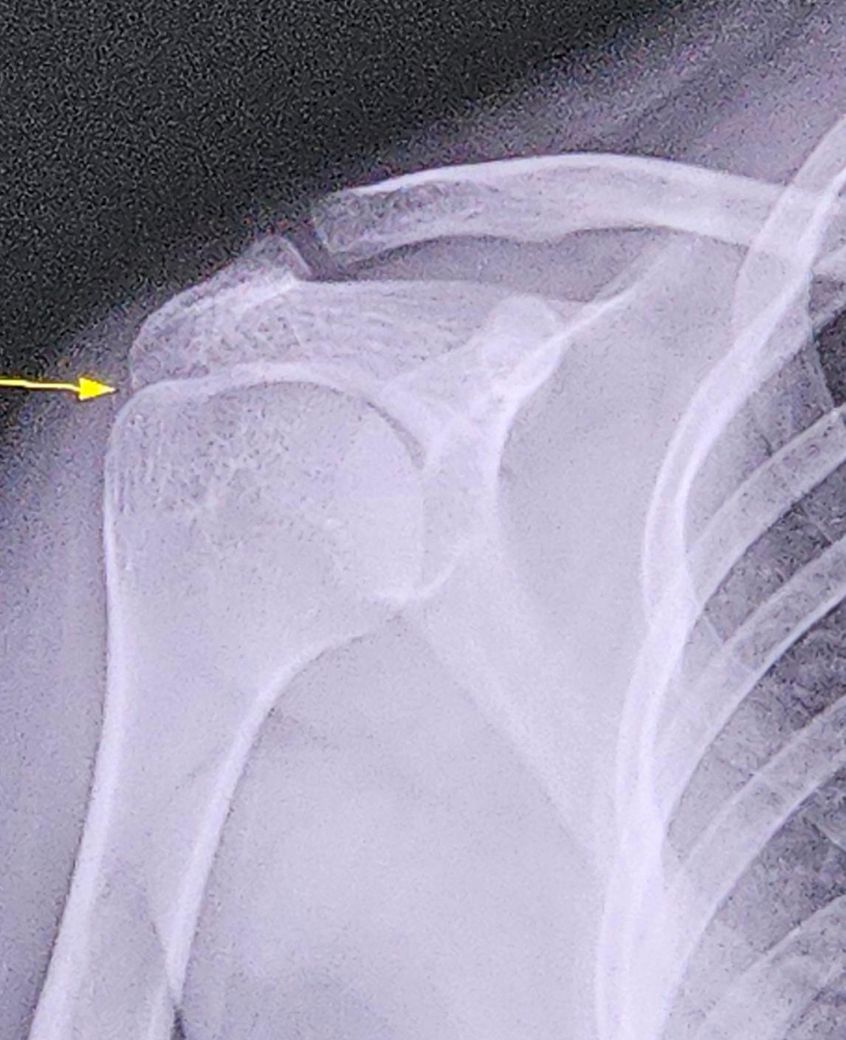

엊그제 배드민턴을 하다가 팔이 꺾이면서 뚝-소리가 났고 팔이 축 늘어지고 엄청 아팠지만 그때 당시에는 다행히 움직이는데 아플뿐이지 팔이 탈골이 되지 않아서 계속 쳤는데요 단순 근육통이라고생각했는데 와 너무 아픈데 하면서 팔을 들수 없을 정도로 아파서 병원을 갔더니 어깨에 틈이 있어야 하는데 틈이 없다며 어깨 염좌 진단을 받았습니다 아마 견봉하 공간이 아예없고 견봉과 대결절뼈가 붙어서 그런것 같습니다 부모님은 배드민턴을 하지 말라고 하셨고 ㅠ 회복기간을 어깨가 다 나을때까지 쉬라고하셨는데 2주 얘기하셨는데 전 3주 쉴생각이고 다 나을지 고민입니다 수행이 골프와 제자리 멀리뛰기 이고 배드민턴은 제가 좋아해서 방과후로 2시간 동안 하는데 배드민턴을 하지 말아야하는건가요..?ㅠ 엑스레이 사진은 밑에 있습니다 ㅠ

• 1번 째 사진

견봉하 공간은 견봉과 상완골 대결절 사이 공간인데 이 공간이 좁으면 회전근개의 염증 압박 손상이 쉽게 생길 수 있습니다.